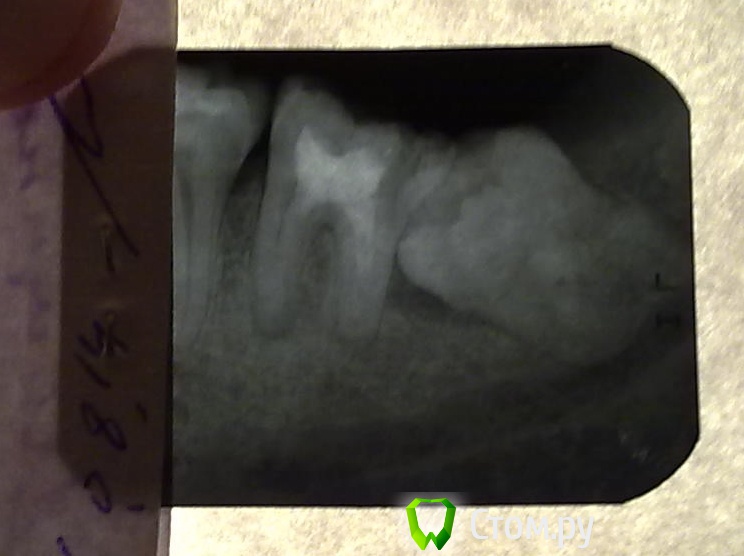

Артём111 Опубликовано 7 августа, 2014 Автор Поделиться Опубликовано 7 августа, 2014 Как смог. Надеюсь, видно. Чуть посветлее и чуть потемнее.Мне 28 лет Ссылка на комментарий

samsonov Опубликовано 7 августа, 2014 Поделиться Опубликовано 7 августа, 2014 Прогноз не очень идеальный для 7 зуба, но зуб мудрости дальше расти не будет. Так что ,стоит перелечивать каналы 7 - го... Ссылка на комментарий

faity Опубликовано 7 августа, 2014 Поделиться Опубликовано 7 августа, 2014 а я бы удалил 8-ой и пролечил 7-ой, но без гарантии, ибо не факт Ссылка на комментарий

faity Опубликовано 8 августа, 2014 Поделиться Опубликовано 8 августа, 2014 Мне сказали, что это не представляется возможным (или не имеет никакого смысла, не помню конкретной формулировки; суть всё-равно уловлена).удаляется 8-ка, в лунку закладывается PRP, ушивается, через 4-6 недель лечится 7-ка, через полгода рентгеноконтроль, по результатам либо ничего, либо лоскутная операция с аугментацией в ретромолярной области. вообще не вижу проблемы в сохранении зуба, поверьте на слово, все те манипуляции которые я описал позволят сохранить вам зуб и съекономить вам денег, потому что имплантация с последующим протезированием намного дороже.как вам такой смысл? Ссылка на комментарий